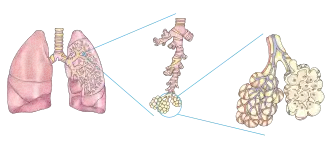

Plicní sklípek (latinsky alveolus, množné číslo alveoli) je dutý útvar v plicích podílející se na struktuře plicních váčků. Představuje základní funkční jednotku plic, ve které dochází k difuzi plynů (oxidu uhličitého z těla a kyslíku do) mezi vzduchem a krví, pomocí kapiláry (vlásečnice) – tedy k vlastnímu dýchání.

Každý plicní sklípek má přibližně 200 mikrometrů v průměru a při nádechu se zvětšuje.[1] Plicních alveol je v každé plíci přibližně 350 milionů a jejich celková plocha se odhaduje na 140 m².[2]